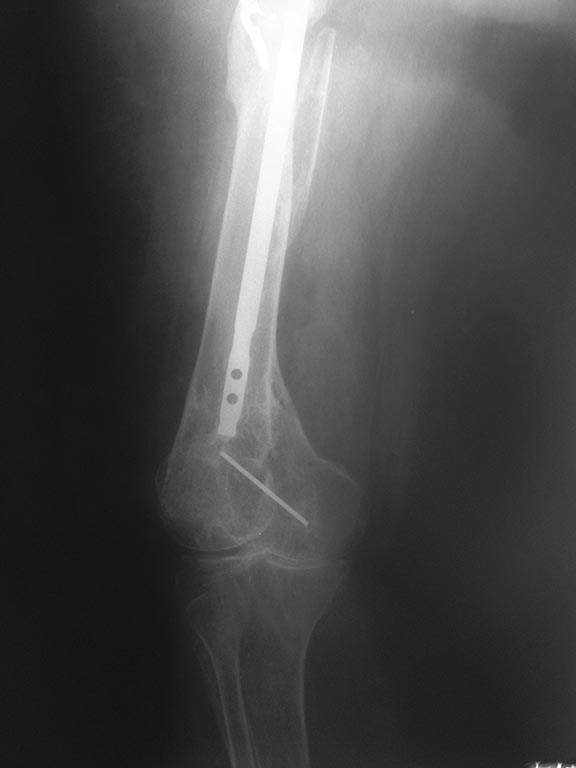

[Ortho] Удаление стержня из бедра перед эндопротезированием?

Имя     : IMG_6568.JPG

Тип     : image/jpeg

Размер  : 39042 байтов

Url     : http://weborto.net:8080/pipermail/ortho/attachments/20170725/b3d50562/attachment.jpe